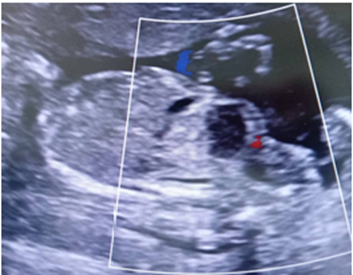

Acudió a la Unidad de Perinatología, realizándose ecografía morfológica del segundo trimestre. Se evidenció en abdomen fetal, por debajo del estómago y adyacente a la vejiga, una imagen hipoecoica de bordes irregulares, que midió 14 x 13 mm, doppler negativo. Se corroboró inserción de cordón umbilical adecuada en abdomen fetal e integridad de la pared del mismo. No se evidenciaron otros hallazgos asociados. Se planteó probable patología gastrointestinal tipo quiste de duplicación intestinal (Figura 1-2).

Figura 1 Ecografía morfológica a las 18 semanas, se observa imagen hipoecoica, irregular que mide 14 x 13 mm (T), vejiga (V).